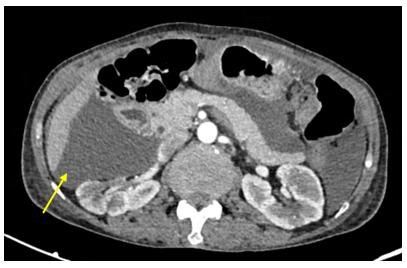

Hình 3: Dịch tự do ổ bụng, chỗ dày nhất 53 mm (mũi tên vàng).

Chụp CT lồng ngực: